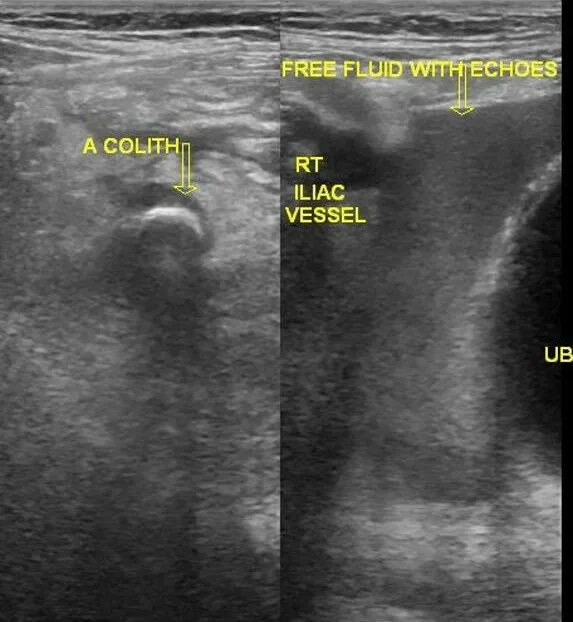

Аппендицит на узи можно ли